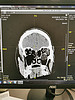

IMG_20211113_071806.